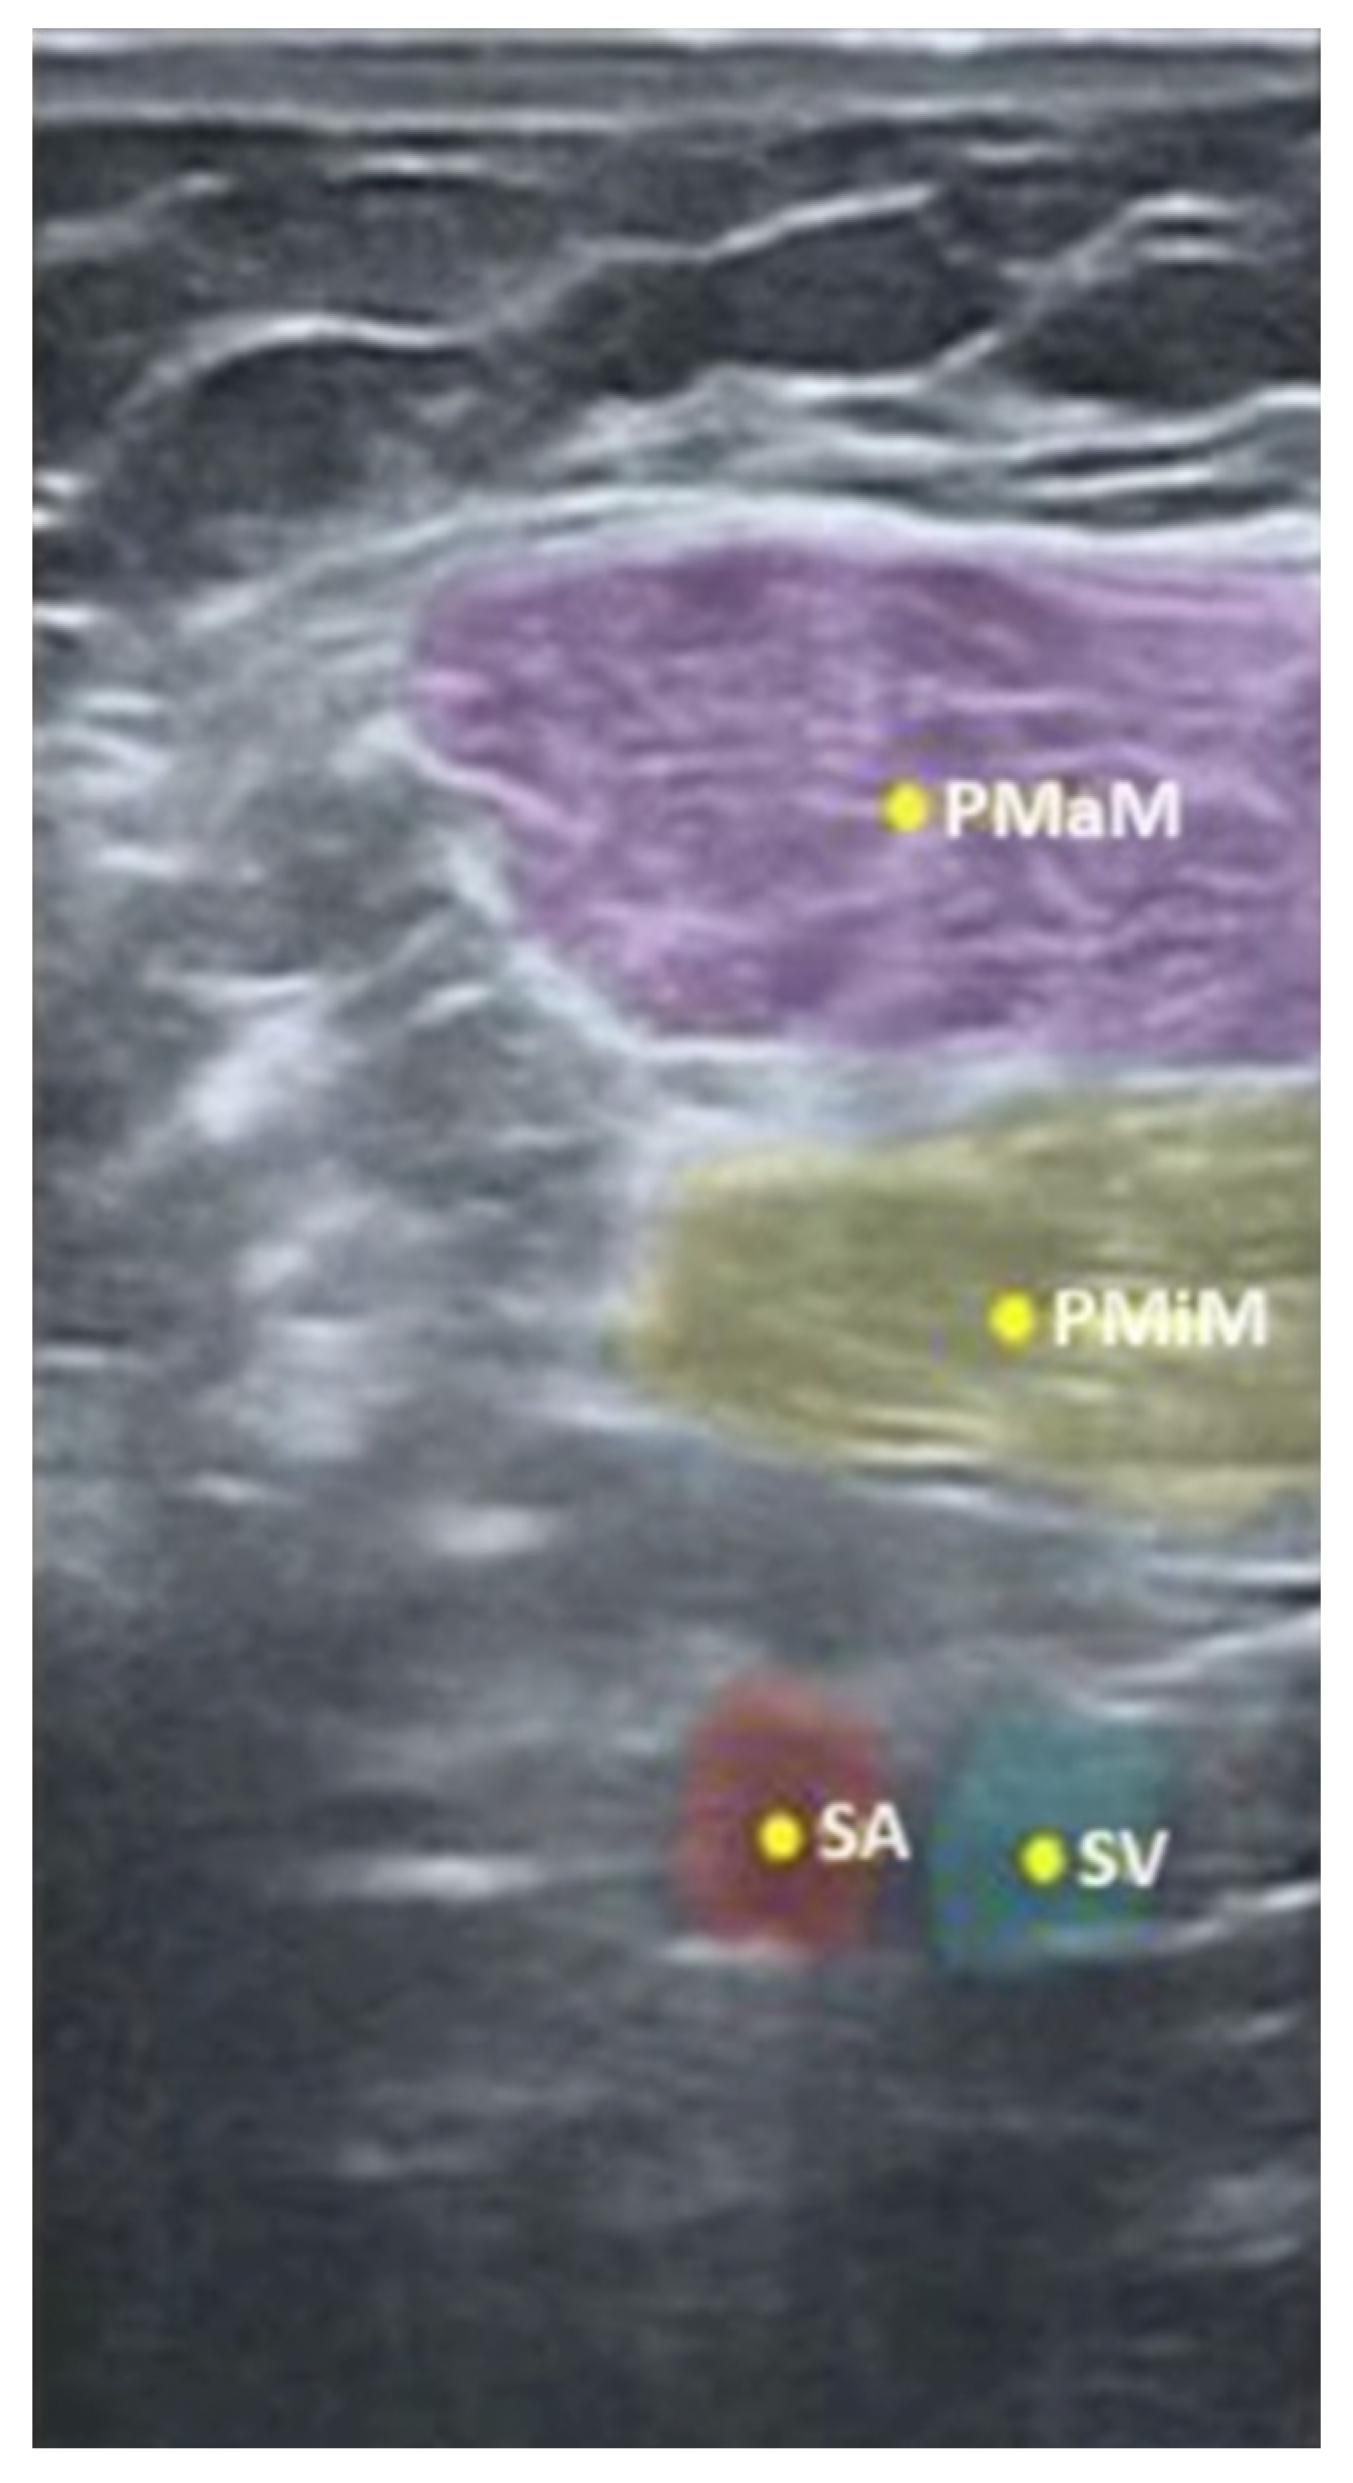

| Infraclavicular | Pectoralis major muscle (PMJ) | 5 ± 0.01 | 4.97 ± 0.08 | 0.95 |

| Pectoralis minor muscle (PMN) | 5 ± 0.01 | 4.98 ± 0.07 | 0.96 | |

| Axillary artery (AA) | 5 ± 0.01 | 4.99 ± 0.05 | 0.99 | |

| Axillary vein (AV) | 4.39 ± 0.26 | 4.95 ± 0.12 | 0.94 | |